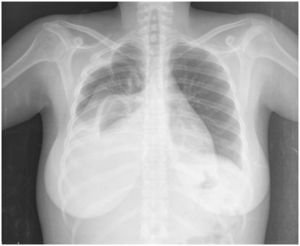

Se concluyó derrame pleural masivo secundario a actividad lúpica, y se trató con prednisona en dosis de 1mg/kg de peso y furosemida, con lo que se logró mejoría.

Se deben descartar otras causas del derrame pleural como infección, embolismo pulmonar, falla cardíaca, síndrome nefrótico o malignidad, antes de emitir un diagnóstico final9. En este caso, el derrame pleural se resolvió sin requerir pleurodesis10.